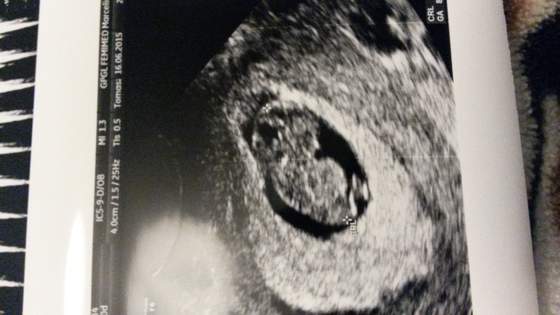

Krwiaka niema;-) dzidzia rozwija sie prawidlowo;-) jest super, mialam lzy w oczach!

Mowil ze terez sie uda i wszystko bedzie dobrze!